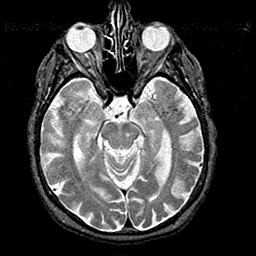

Alzheimer's disease MR T2-weighted -- Slice #18

[Home][Help][Clinical][Tour 1][Tour 2] Slice 18